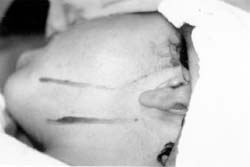

Paciente masculino de 8 años de edad, natural y procedente de Bogotá, D.C.; remitido del hospital de La Victoria para valoración y manejo de secuela por osteomielitis mandibular. Al servicio de cirugía oral y maxilofacial del hospital occidente de Kennedy.

Como antecedentes personales de importancia clínica: Osteomielitis mandibular a la edad de 7 años, con manejo quirúrgico consistente en secuestrectomía hemimandibular izquierda y germinectomia de dientes permanentes realizado en el Hospital de la Misericordia.

Al examen físico de ingreso, paciente con levognatismo mandibular, deformidad de contorno, defecto óseo mandibular ipsilateral, hipometría bucal ( 20 mm ), limitación a las excursiones laterales y protrusivas, deflexión mandibular derecha a la valoración ATM, no evidencia clínica de proceso osteomielítico activo. (Fig. 8)